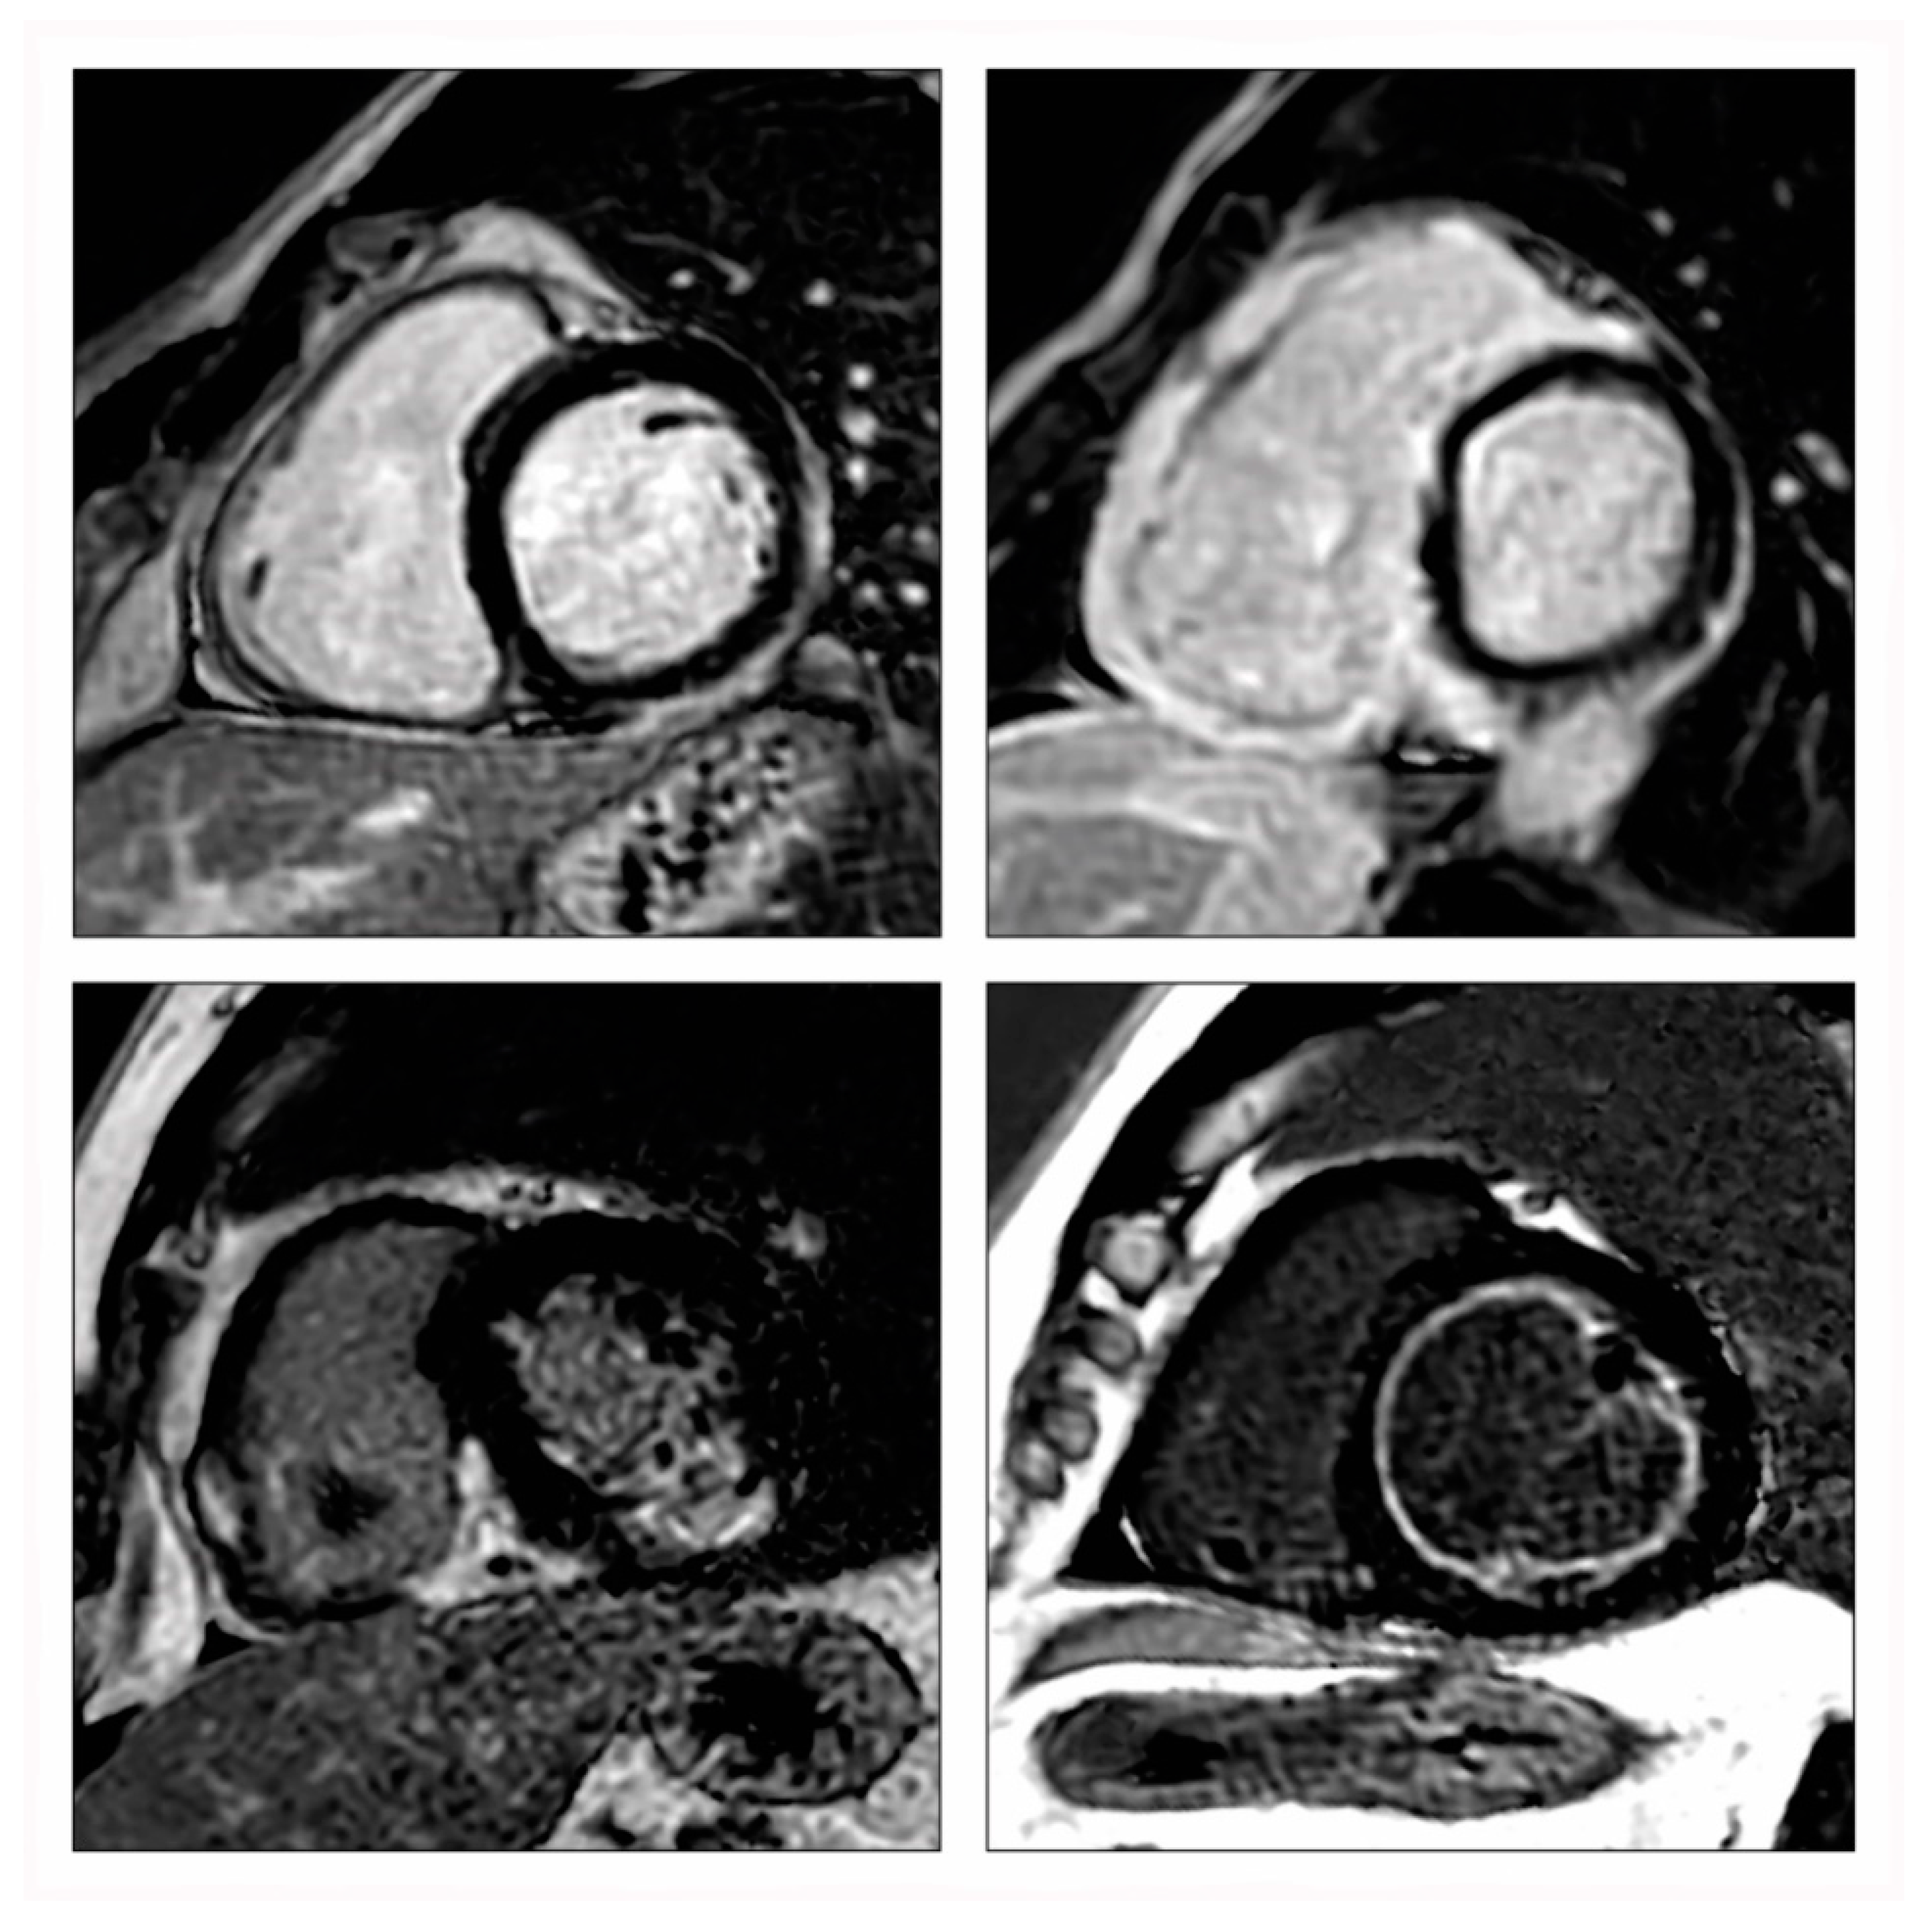

3.1. CMR Mapping Techniques

3.2. Myocardial Oedema

3.3. Myocardial Hyperaemia and Capillary Leak

3.4. Myocardial Necrosis and Fibrosis

4. Updated Lake Louise Criteria